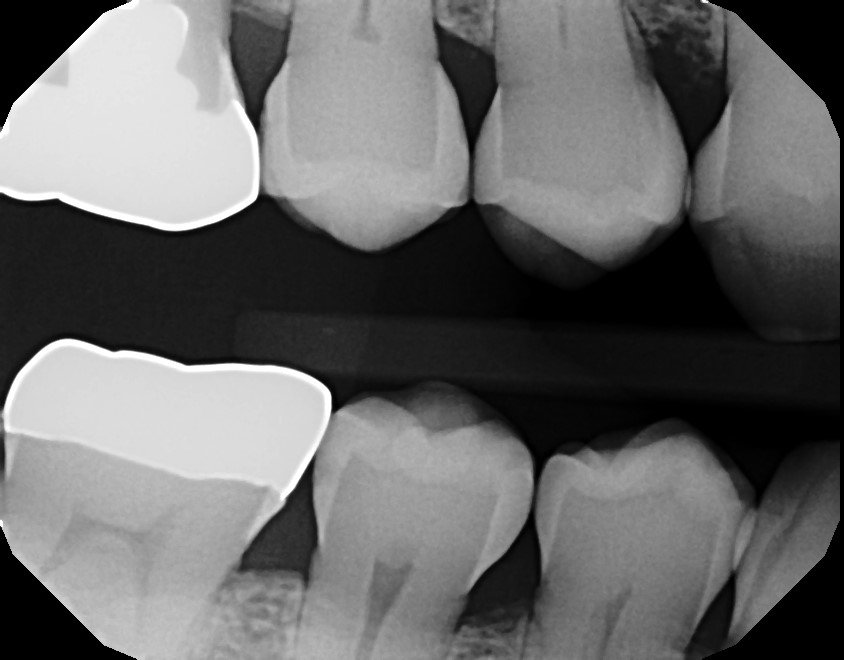

Well, last week it hit home for me. A longtime patient and friend of our practice stopped in for his routine exam and cleaning. As I reviewed his radiographs, I saw a fairly significant bit of decay on his #29(lower right bicuspid). Since we diagnose with digital radiographs, I was able to see his history with in this area of his dentition. As I looked at his exam from late 2019, all of the bits of broken teeth, exacerbated gum disease, and “surprise” cavities solidified for me.